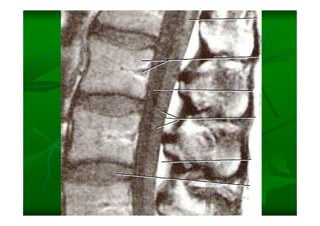

Este documento describe la columna vertebral humana. Está compuesta de 33 vértebras divididas en 7 cervicales, 12 torácicas, 5 lumbares, 5 sacras y 4 cóccigeas. Cada vértebra posee un cuerpo, pedículo, apófisis transversas, apófisis espinosa e inferior y laminas. Las curvaturas de la columna son la lordosis cervical y lumbar y la cifosis torácica y sacra.